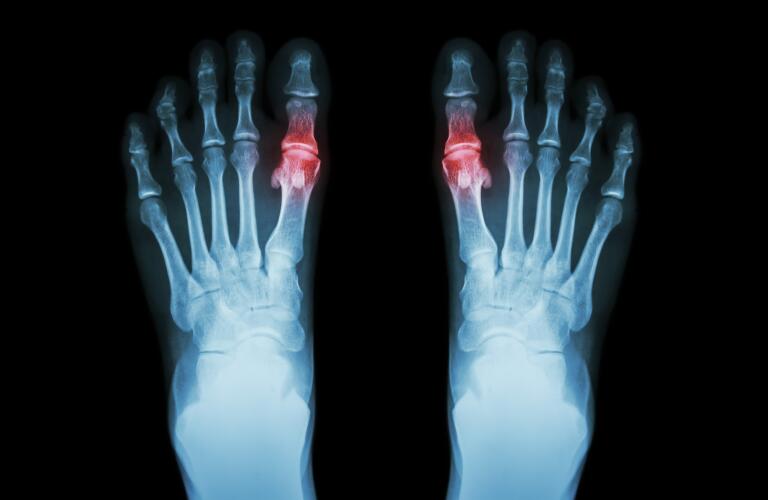

La gota, una forma distinta de artritis, a menudo se reconoce por sus ataques repentinos e intensamente dolorosos, afectando más notoriamente el dedo gordo del pie. Esta inflamación particular del dedo gordo del pie, clínicamente denominada podagra, es un síntoma distintivo que se manifiesta en algún momento hasta en el 80% de las personas diagnosticadas con gota. Si bien el dedo gordo del pie es un sitio inicial común, es crucial comprender que la gota es una afección progresiva que avanza a través de distintas etapas, desde sus orígenes bioquímicos sutiles hasta un estado crónico más debilitante. Cada etapa presenta desafíos únicos y requiere consideraciones específicas para su manejo, lo que subraya la importancia de comprender el curso de esta enfermedad.

La transición de la hiperuricemia asintomática a la gota aguda marca el inicio de los característicos ataques dolorosos. Durante esta etapa, el ácido úrico excesivo en la sangre comienza a cristalizarse, formando estructuras microscópicas en forma de aguja de urato monosódico (UMS). Estos cristales afilados se acumulan principalmente dentro del líquido sinovial y el cartílago de las articulaciones, desencadenando una potente respuesta inflamatoria. Si bien el dedo gordo del pie es el sitio más frecuentemente afectado, lo que lleva a la afección conocida como podagra, estos cristales dolorosos también pueden depositarse e inflamar otras articulaciones, incluidos los tobillos, los pies, las rodillas y las muñecas, causando una incomodidad significativa y limitando la movilidad.